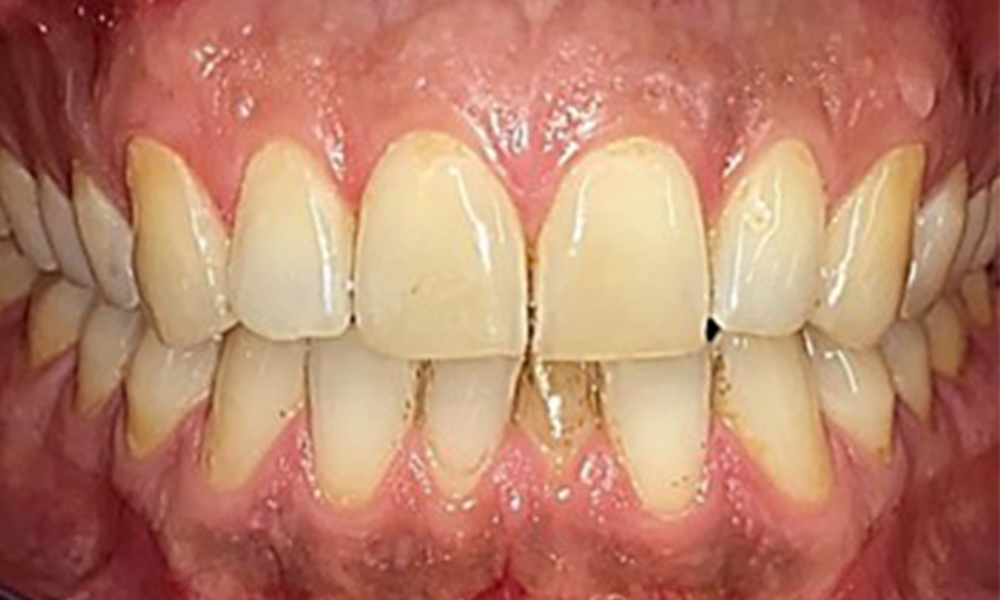

Il n'y a pas eu de résultats pathologiques extra-oraux. Lors de l'examen intrabuccal, l'inspection de la vue frontale a révélé une décoloration brunâtre près de la gencive kératinisée et à la transition vers la muqueuse mobile (Fig. 2), qui pourrait être attribuée à la consommation de nicotine. Des lésions blanchâtres de la muqueuse ont été observées sur le palais, en particulier près des surfaces palatines des molaires maxillaires, ce qui indique une kératinisation accrue et peut également être attribué à la consommation de nicotine. La langue était recouverte d'un enduit amovible blanc et brunâtre.

Le patient a une dentition complète avec un total de 28 dents. Il y avait des érosions et des attritions notables. (Fig. 4, Fig. 5). En raison du bruxisme, le patient a porté pendant de nombreuses années une attelle avec une gouttière ajustée la nuit. Les érosions ont été causées par une consommation prolongée de boissons isotoniques. Aucune perte d'os parodontal ou carie active n'a été observée.